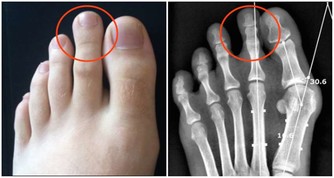

2、嚴禁吸毒:

吸毒不僅違反法律,還會危害生命,感染艾滋病毒的機率也會大大增加,因為吸毒者免疫機制很差,非常有利於艾滋病病毒的侵襲。

3、不共用注射器:

共用注射器是很危險的,如果注射器中帶有艾滋病病毒,病毒很容易隨著輸液進入人體。

4、切斷血液傳播:

不要擅自輸血和使用血製品,要在醫生的指導下進行,以免感染。